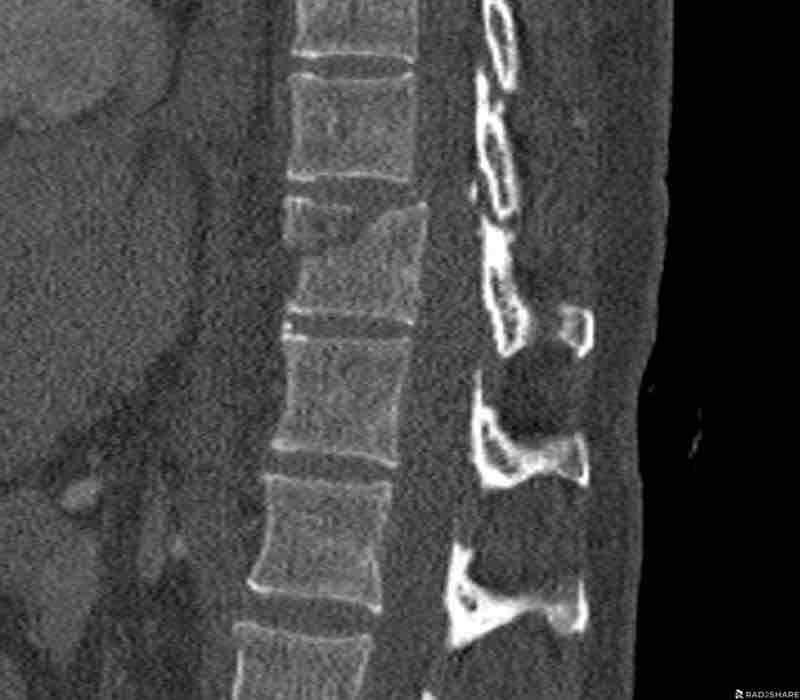

This is a difficult case with injuries at many levels.

What is the most severe level for classification.

Then continue with the second stack below for classification of other levels.

Findings

- The most severe level is L4/5 with dislocation (dotted lines)

- Facet fractures at L4 (arrows).

- A4 burst fracture (circle).

Conclusion:

Injury type C + A4 at L4/5.

Continue with the next stack of images to classify level L2…

Scroll through images.

What is the highest AO-level?

- No dislocation ( no C type).

- Mainly horizontal fractures of spinous processus at multiple levels (B-type).

- Split fracture L2 (type A2).

Conclusion

Injury type B2 + A2 at level L2.